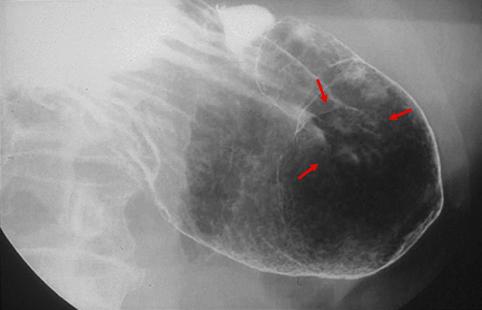

疾患(病理主体)の分類悪性上皮性腫瘍/腺癌

部位(臓器別)胃(部位)/胃角

検査方法X-P

腫瘍の肉眼分類0型(表在型)/IIa型(IIa+IIc)

病変の最大径(ミリ)30〜34

腫瘍の深達度m